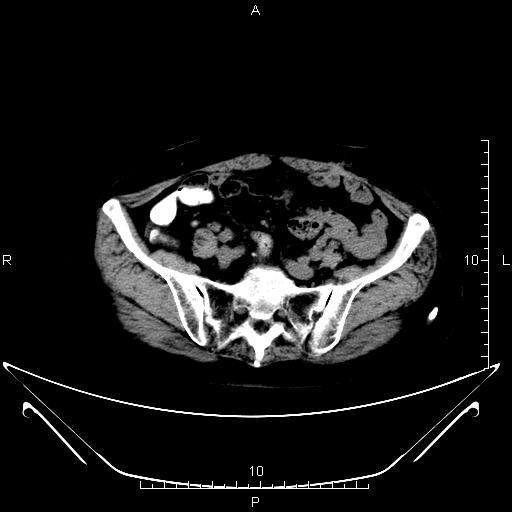

CT51466:盆腔CT

本帖最后由 cefcmj 于 2015-12-26 21:33 编辑 女,72岁,直肠癌术后半年CT检查。

1)直肠术后改变。2)骶前筋膜明显增厚,且与直肠后壁(相当于直肠吻合口处)带状软组织密度影相连,增强后轻度强化;考虑肿瘤侵犯(转移)所致。

考虑吻合口复发

吻合口上段可疑复发,建议行肠镜进一步观察。